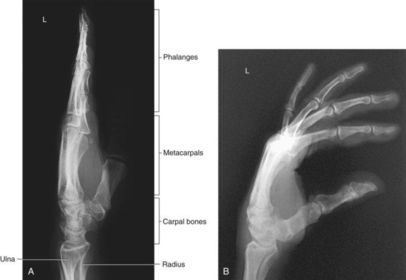

| L | CRITERIA: radius/ulna should be superimposed thumb should be forward metacarpals superimposed POSITIONING: CR perpendicular @ midcarpals |